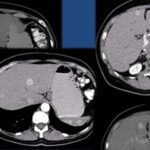

Las recomendaciones estándar para el diagnóstico de CHC incluyen TC multifásica o RMN, que son modalidades beneficiosas para resaltar características únicas de CHC (Anexos 12 y 13). Las diferencias fisiológicas en la perfusión sanguínea entre lesiones hepatocarcinogénicas y tejido no neoplásico muestran diferencias distintivas en las características de imagen utilizando exámenes de contraste multifásico.(23) Las fases consisten en arterial hepática tardía (20-40 s), venosa portal (60-90 s) y retardada (35 min). La fase arterial tardía es útil para detectar lesiones hipervasculares con lesiones de CHC que realzan característicamente en relación con el parénquima hepático circundante. El realce de la lesión arterial se puede apreciar dentro de lesiones tan pequeñas como 1 cm. Dentro de las fases venosa portal y retardada, se observa comúnmente lavado o hipointensidad para las lesiones de CHC. Durante la fase retardada o de equilibrio, se pueden visualizar otras características de CHC como características de la cápsula (p. ej., lavado de la lesión con realce de seudocápsula) y arquitectura en mosaico. La introducción de agentes de contraste basados en gadolinio (gadobenato de dimeglumina y ácido gadoxetato) puede ayudar a la categorización LI-RADS.(19) Estos agentes son absorbidos por los hepatocitos del parénquima hepático normal y hay poca absorción en hepatocitos no funcionales o disfuncionales, como el caso del CHC. Los agentes basados en gadolinio funcionan de manera similar a los agentes extracelulares, pero pueden ayudar en el diagnóstico de lesiones con características atípicas (p. ej., sin lavado, hiperrealce arterial) o distinguir el CHC de las seudolesiones. Por ejemplo, estos agentes permiten una fase hepatobiliar posterior al contraste adicional, que mostrará una mayoría de lesiones de CHC (90%-95%) como hipointensas en relación con el parénquima hepático hiperintenso circundante.(23)

Se recomienda la RMN para la estadificación de la enfermedad de CHC, dado que algunos informes han estimado que la TC subestima el 52% de los casos.(23) La RMN también tiene una eficiencia diagnóstica superior a la TC en la detección de lesiones pequeñas (≤ 3 cm). Sin embargo, la TC está más fácilmente disponible que la RMN, y las limitaciones para usar la RMN, incluidos mayores costos y complejidad técnica, hacen de la TC una alternativa diagnóstica complementaria. Un informe mostró que el uso combinado de TC/RMN proporciona una mejor precisión diagnóstica en la caracterización de lesiones hepáticas utilizando LI-RADS (91,29%) que la RMN (85,37%) o la TC (67,6%) solas, pero los protocolos combinados deben limitarse a casos difíciles o inciertos para justificar su uso.(21-23)